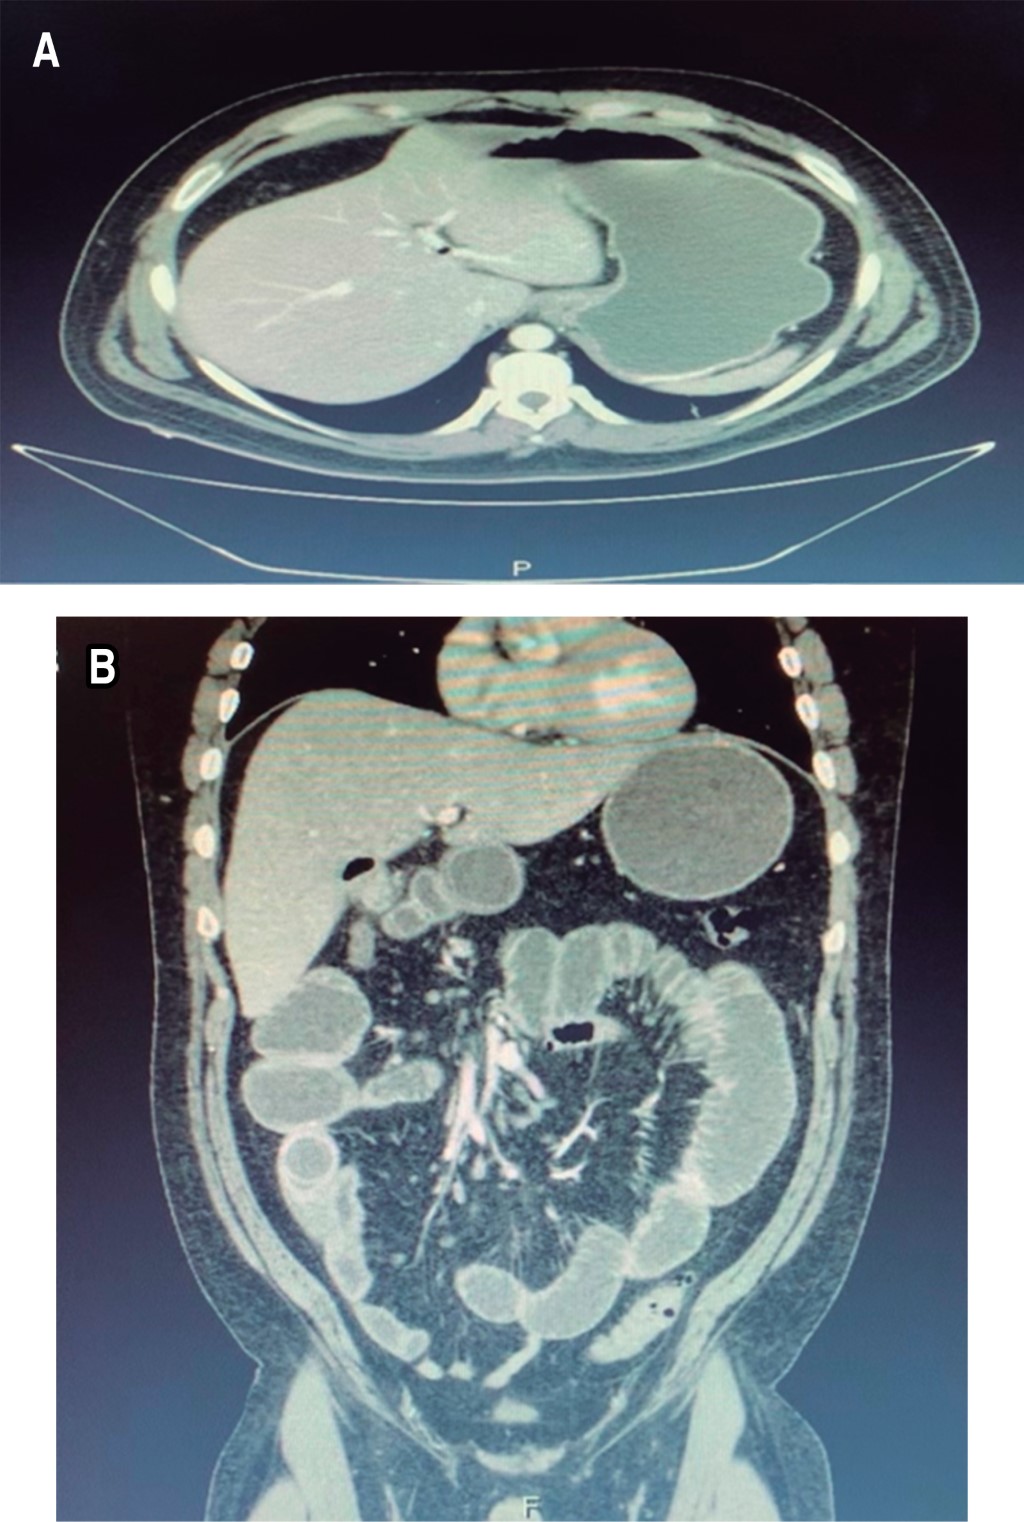

Se tuvieron como hallazgos transoperatorios: distensión de asas de íleon y yeyuno de manera generalizada, lito vesicular de 3 cm impactado a 90 cm de la válvula ileocecal, lo que condicionó oclusión intestinal alta. Apéndice cecal sano, vesícula biliar no palpable, escaso líquido de reacción.

Se decidió realizar enterolitotomía con extracción de lito y cierre primario en dos planos con técnica de Connell-Mayo con poliglactina 910 de tres-cero aguja atraumática y sutura interrumpida de Lembert con seda y aguja tres-cero atraumática, así como colecistectomía diferida (Figura 3). Se colocó un drenaje de tipo Penrose de media pulgada hacia el hueco pélvico y se cerró por planos con poliglactina 910 del 0 para la pared y cierre de piel por medio de puntos simples con monofilamento Nylon Preto tres-cero.

El tratamiento de esta patología es quirúrgico; no obstante, se inicia con medidas de rehidratación y corrección de desequilibrios ácido-base y electrolíticos. A su vez existen dos opciones terapéuticas: por un lado, enterolitotomía con extracción del cálculo y colecistectomía diferida, y por el otro, enterolitotomía, colecistectomía y cierre de fístula en un solo tiempo quirúrgico.2,3,8 La primera opción representa menor riesgo quirúrgico y muchas veces se prefiere, ya que son pacientes de edad avanzada con múltiples comorbilidades y se realiza con mayor frecuencia.1,3 A pesar de no ser un paciente con comorbilidades y estar estable al momento del evento quirúrgico, decidimos realizar enterolitotomía longitudinal en el borde antimesentérico del íleon con enterorrafia transversal en dos planos y colecistectomía en un segundo tiempo quirúrgico, puesto que consideramos que ésta tiene mejores resultados con base en lo reportado por la literatura.

Figura 3